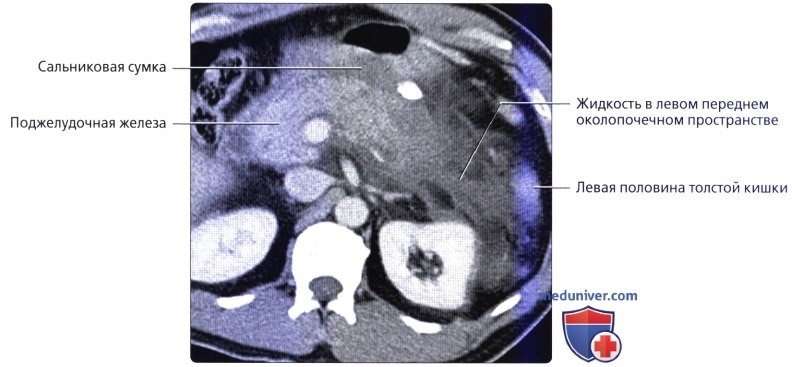

УЗИ диагностика кольцевидной поджелудочной железы: что важно знать